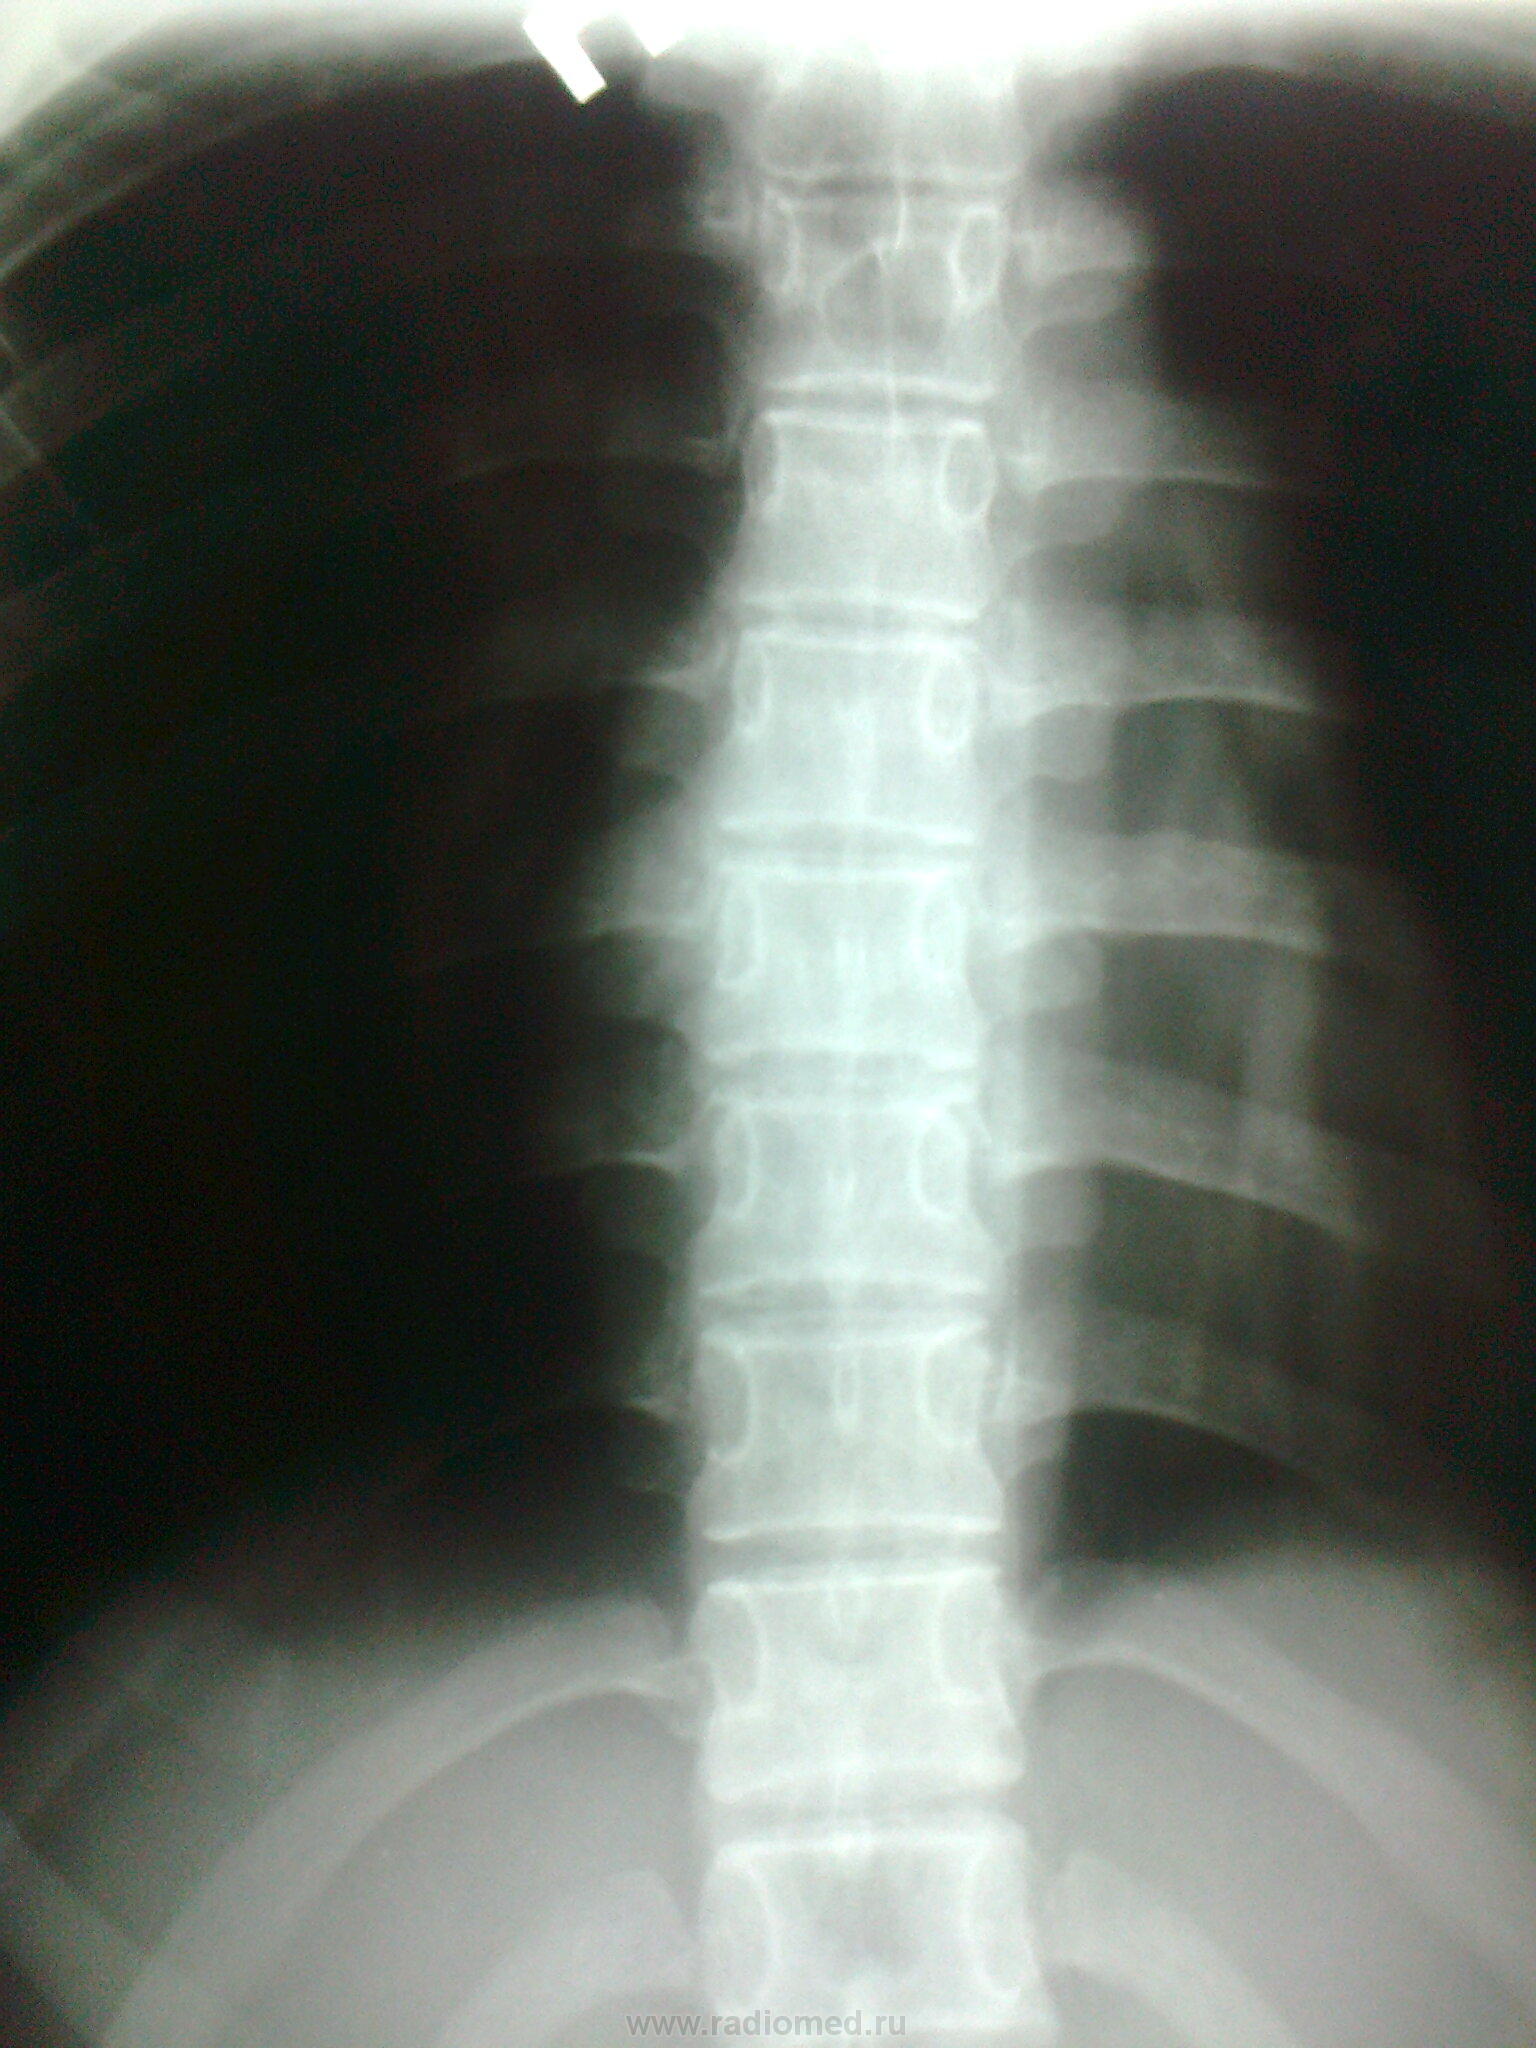

"Дырка" наслаивается на тень позвонка. Откуда?

Вот и я думаю- эта "дырка" в теле или в остистом отростке. В ОАК -норма.. Девушка из благополучной семьи, учится в медучилище. Направила на МРТ?

В теле позвонка образование с четким склеротическим ободком. На боковом видно, по моему это Th5.

Точно, я тоже указала Th5  киста?

Ну глазастая!yes Ну точно тут КТ надо. Т.к. м.б. и гемангиома и гемангиолипома и киста костная.

Андрей Викторович, здравствуйте. "Дырку" нашла на рентгенограммах, а флюшку - для профилактики, т.к были боли в гр.клетке; изменения -то нашла в ТЕЛЕ Th5, а по КТ- в основании остистого отростка (суперпозиция)

Здравствуйте Татьяна! На МРТ очень плохо видно, в первую очередь дифференцировал бы между аневризмальной костной кистой и остеобластомой, более вероятно первое

Дима, здравствуйте.Пациентка конс.онкологом DS: Эозинофильная гранулема остистого отростка Th 5, конс.радиологом, гематологом - выполнена пунция грудины-с пов.лейко-эритробластических клеток, нейрохирургом - лучевая терапия в настоящее время не показана, лечится в реабилитационном центре, болевой с-м купирован. Вставляю прококол-заключение.